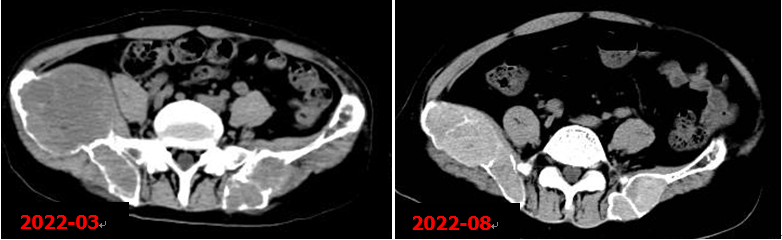

右側(cè)甲狀旁腺腺瘤切除術(shù)后,甲狀旁腺M(fèi)IBI顯像未見明確病灶組織殘留征象。術(shù)后5個(gè)月本院復(fù)查CT示右髂骨病變明顯縮小。